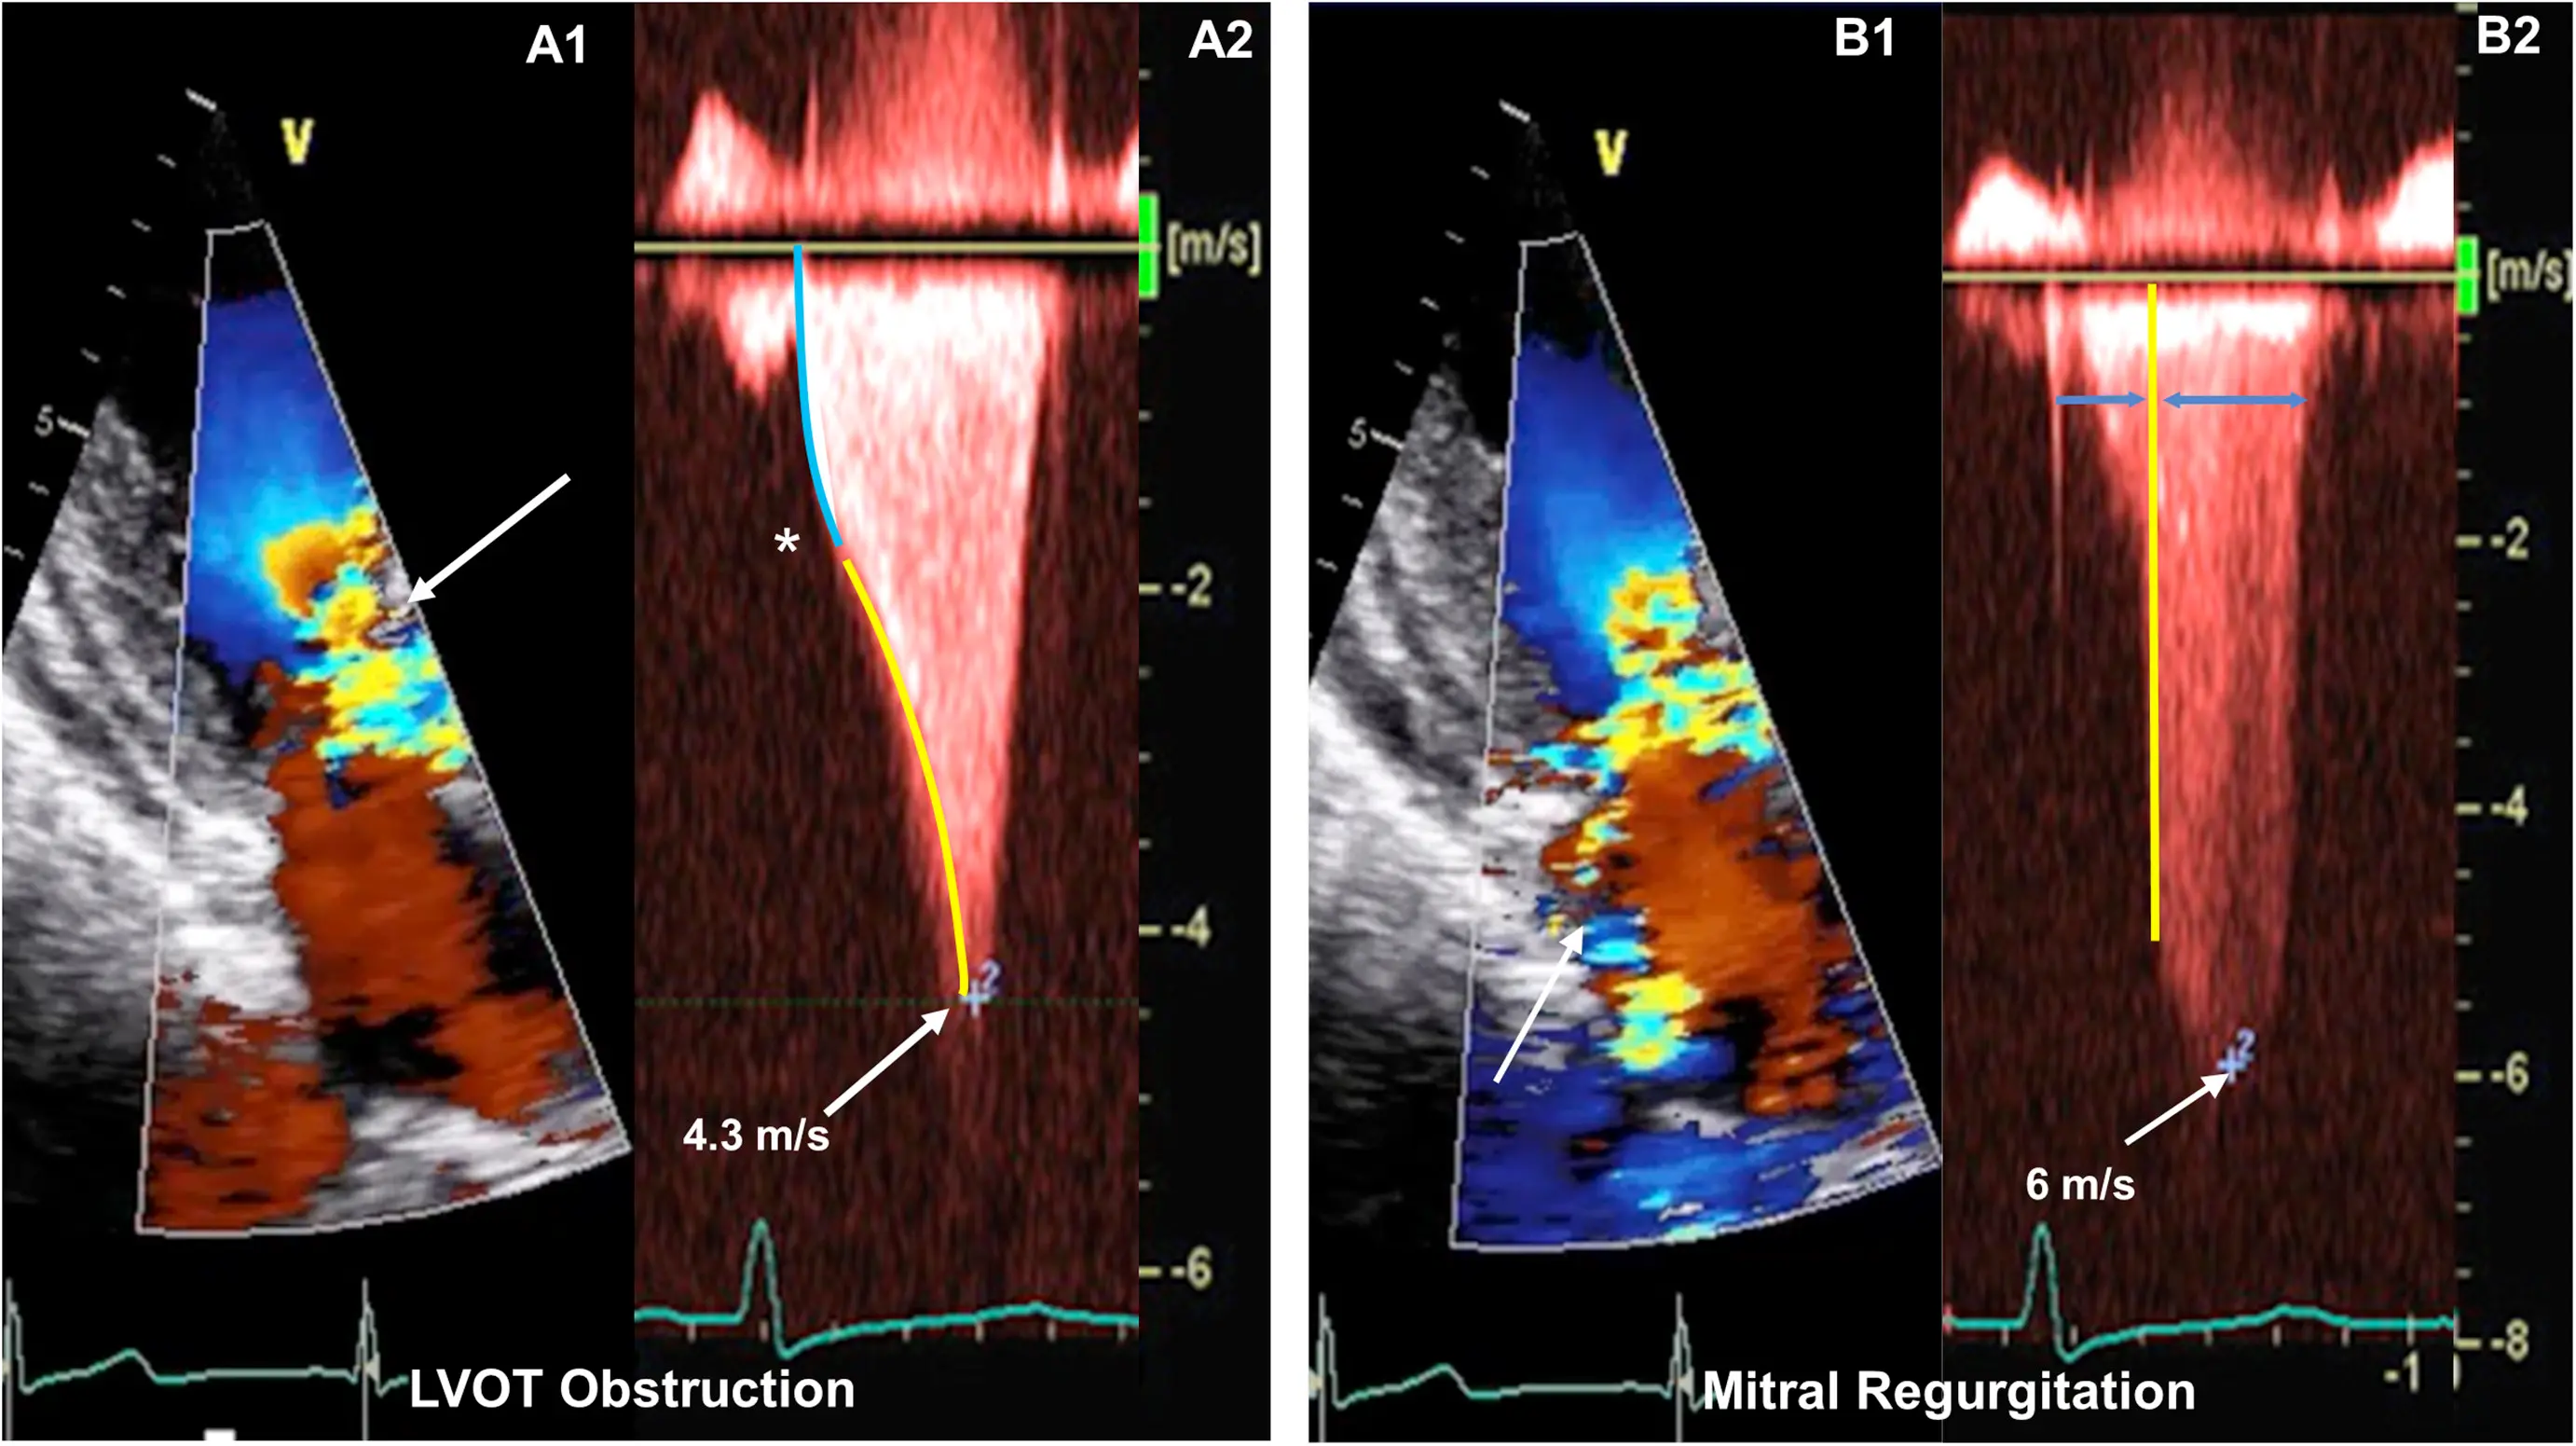

M-mode

- Temporal resolution of M-mode → the duration of SAM where it is in contact with the septum correlates w/ severity of LVOT obstruction

- M-mode in the parasternal long-axis view may assess for midsystolic notching of the aortic valve, reflecting very rapid ejection of LV stroke volume in early systole followed by attenuation of stroke volume in the obstructive phase.

Notice the turbulence, which suggests LVOTO